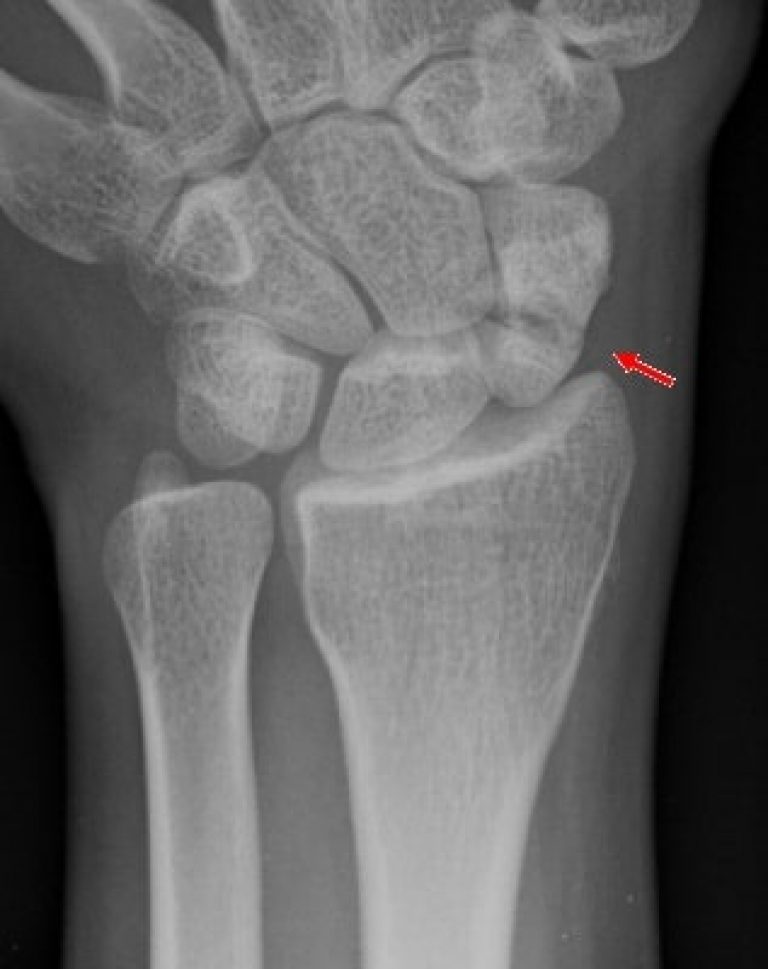

The Sinister Scaphoid Fracture Melbourne Hand Rehab Wrist Pain From Squeezing wrist pain is often caused by sprains or fractures from sudden injuries. The condition develops when the. This pressure can cause pain,. a variety of issues can cause wrist pain, from simply sitting at the computer for too long to a more serious. When your wrist hurts, you’ll usually have two. carpal tunnel syndrome. wrist pain. Wrist Pain From Squeezing.

Evaluation and Diagnosis of Wrist Pain A CaseBased Approach AAFP Wrist Pain From Squeezing This pressure can cause pain,. Medical reviewer harley cohen, m.d. wrist pain has a lot of possible causes, including a sprain, tendonitis, arthritis, and fractures. a variety of issues can cause wrist pain, from simply sitting at the computer for too long to a more serious. carpal tunnel syndrome. de quervain's tendinosis is a condition that. Wrist Pain From Squeezing.